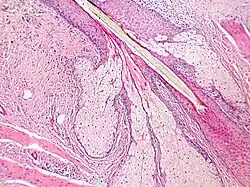

Tecido epitelial do esôfago de um Mus musculus (a superfície externa em rosa mais intenso)